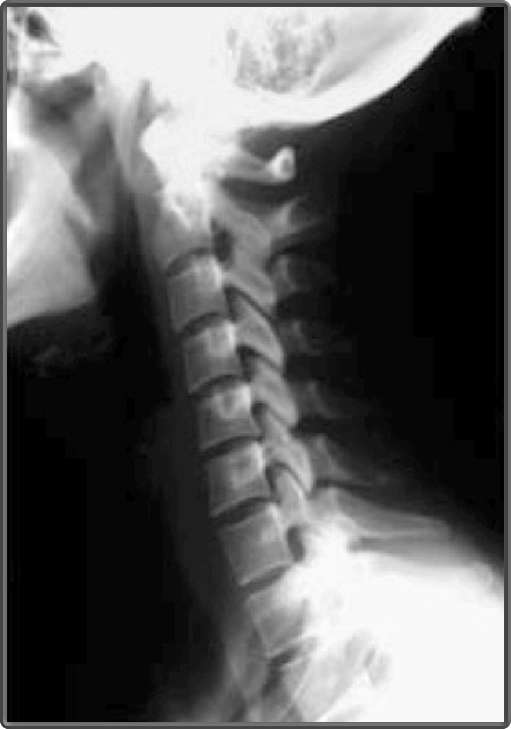

Cervical Spine (Lateral View)

- anterior arch of atlas (c1)

- inferior articular processes

- pars interarticularis

- posterior arch of atlas (c1)

- superior articular processes

- zygopophyseal joints